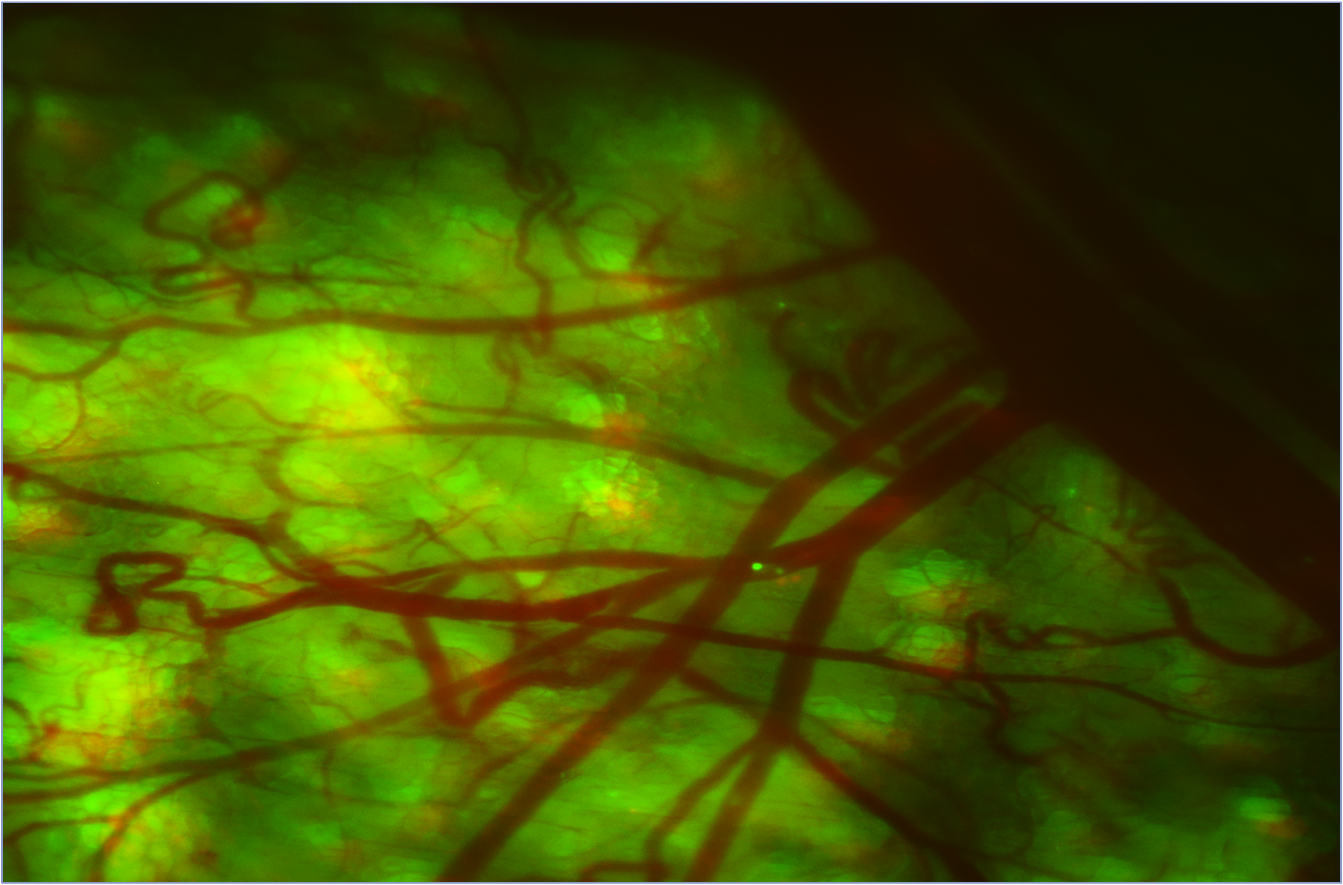

Dan Bukaty, president at PG&O, notes that as scientists are discovering more and more on the nanoscale, optics become even more and more important. So, the ability to look at these things with different wavelengths of light provides greater opportunities for optics and optical coatings. “Due to the specificity and quantifiable nature of fluorescence imaging, optical filters and mirrors have risen in performance to meet the market need for optics that provide high performance and spectral complexity over an ever increasing fluorescent probe range,” says Nick George, director of product marketing at Semrock. George notes that the latest optical filters have improved the sensitivity, resolution, and speed of fluorescence instruments. Also, optical filters and filter sets that offer tunable angles enable spectral adjustment without polarized light separation—a limitation common in trending microscopy applications (see Fig. 2).Biomedical trends